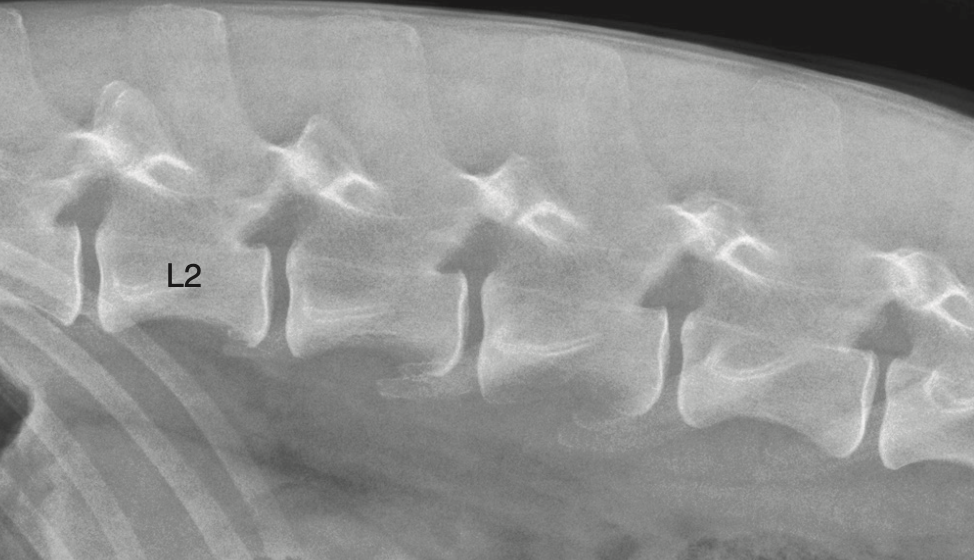

The pars lumbalis of the diaphragm attaches to which vertebrae in dogs?

C) L3 and L4

The right and left crura of the pars lumbalis attach to the cranial ventral border of L4 and the body of L3.

Where do the crura of pars lumbalis attach?

L3 body / L4 cranioventral border

Which part of the diaphragm attaches to L3/L4?

Pars lumbalis crura

2) Which of these statements is false about the pars lumbalis a) It attaches to the cranioventral border of L4 b) It is the part of the diaphragm that makes up the right and left crura c) The Attachment area on the vertebrae can appear indistinct and be mistaken for bone lysis d) It attaches to the body of L2 and 3

2) D only to l3 and l4

- Central tendinous part - Peripheral muscular part (3 areas) Pars sternalis =\> attaches to xiphoid cartilage Pars costalis =\> attaches to 8-13th ribs Pars lumbalis =\> 2 crura. R attaches to craionventral border L4, L attaches to body of L3